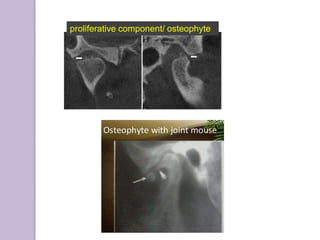

RADIOGRAPHICALLY:

Degenerative

component

Ely cysts

Erosions of condylar head , posterior

slope of articular eminence.

Large glenoid fossa

Small, round , radiolucent

areas with irregular margins

surrounded by areas of

increased density, deep to the

articulating surfaces

Sharp pencil shaped

condyle

proliferative component/ osteophyte